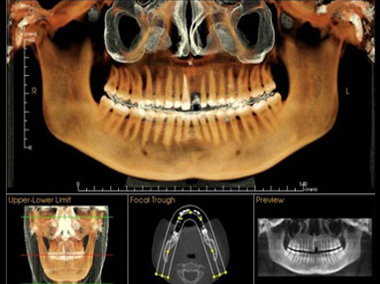

口腔影像中心

我们的牙齿,平时能看到的仅是“冰山一角”。

即使是经验再丰富的口腔医生,想要仅凭肉眼看清牙齿或颌骨病变的全貌,也是不可能的事;为了让口腔治疗更加精准,必须借助影像的力量。

这里同样配备国际一流设备:

两台卡瓦CBCT(i-cat、Op300-1)

两台全景/侧位机(Pan eXam Plus)

两台卡瓦牙片机(FOCUS)

一台DR